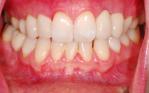

Harriet

Orthodontic closure of the front gap and replacement of the loose baby teeth with some permanent implant crowns and bridgework.

Before